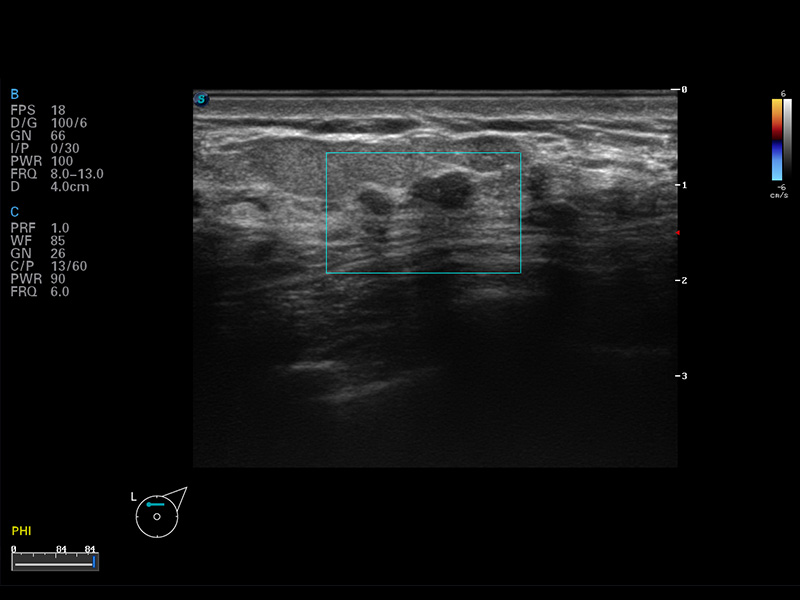

成像技術(shù)

實(shí)時(shí)寬景成像

空間復(fù)合成像